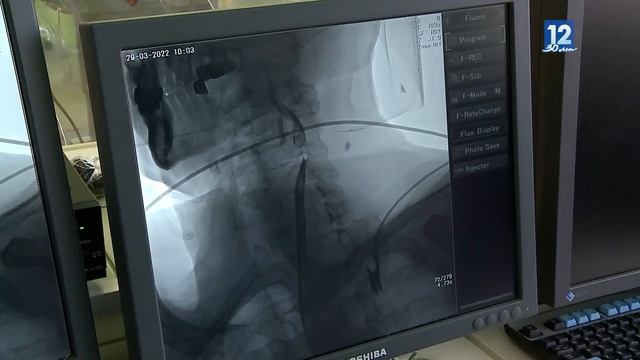

24 операции по извлечению тромбов из сосудов головного мозга провели врачи в Череповце